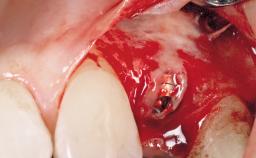

Late Flapless Placement of an Implant in a Maxillary Left Central Incisor Site

A 39-year-old male patient presented with a chief complaint of discomfort and gingival discoloration around his maxillary left central incisor. He was in good general health and was a non-smoker. His past dental history was significant because of the traumatic fracture of tooth 21 in a sporting accident at age 13. Initial dental treatment included endodontic therapy and a full-coverage restoration. The patient became symptomatic 5 years later, when structural failure of the tooth resulted in the dislodgment of the crown. Endodontic retreatment, apical surgery, and post-and-core restoration were performed.

Bone Volume Deficient horizontally, requiring prior grafting